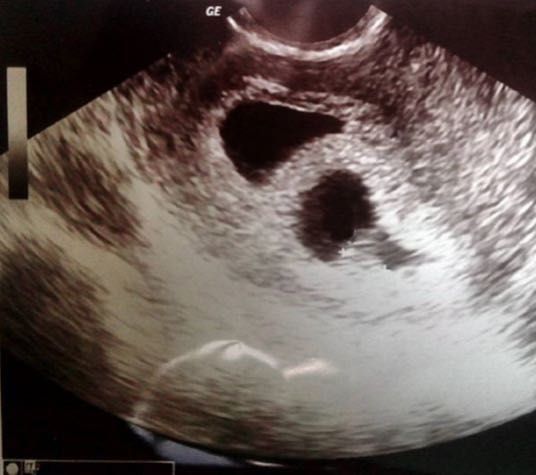

Observen que bellos ecos (Luis Fernando, Luis Alonso) así se llamarán:

Este último lo escaneo para agregarle que los ama.